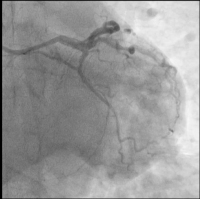

CX

Abbildung 3: CX: chronischer Verschluss eines Marginalastes

CX: Ballon

Abbildung 6: CX: Ryurei 1,25/15 mm Ballon (Terumo) sowie NEON™ 2,0/20 mm Ballon, anschließend SELUTION SLR™ 2,0/20 mm DEBs